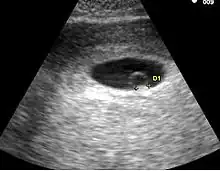

L'aspect échographique du tout début de grossesse

• Le premier signe échographique d'une grossesse est la visualisation d'un sac ovulaire. Il est visible entre 4 semaines et 1 jour et 4 semaines et 3 jours; Il mesure alors 2 à mm. L'utilisation de la voie endovaginale est souvent nécessaire pour le voir. Le sac ovulaire a l'aspect d'une petite tache noire, excentrée par rapport à la cavité utérine, correspondant à la cavité chorionique entourée d'une couronne d'échogénéicité forte : le trophoblaste.

• À cinq semaines, le sac ovulaire mesure mm. Il est quasiment toujours visible lors de l'échographie par voie abdominale. Il est parfois difficile d'affirmer la localisation intra-utérine de la grossesse en raison de l'aspect de pseudo-sac gestationnel décrit au cours des grossesses extra-utérines. Seuls deux signes sont pathognomoniques de la grossesse intra-utérine

• L'aspect en double cercle du sac (double decidual sac sign) correspondant une couronne hyper-échogène interne en rapport avec la trophoblaste et une couronne hypo-échogène externe en rapport avec la transformation gravidique de l'endomètre

• La visualisation de la vésicule vitelline qui affirme définitivement le caractère ovulaire de l'image échographique.

• La visualisation de la vésicule vitelline est un élément essentiel pour affirmer le caractère ovulaire de l'image et l'évolutivité de la grossesse. Embryologiquement, la vésicule vitelline visualisée correspond à la seconde vésicule vitelline. La vésicule vitelline est toujours visible à 5 semaines et 5 jours par voie endovaginale. Le sac ovulaire mesure en moyenne mm. Par voie abdominale, elle est toujours visible à 7 semaines (le sac ovulaire mesure en moyenne 20 mm). Le diamètre de la vésicule vitelline augmente de 5 à 10 semaines pour atteindre 5 à mm.